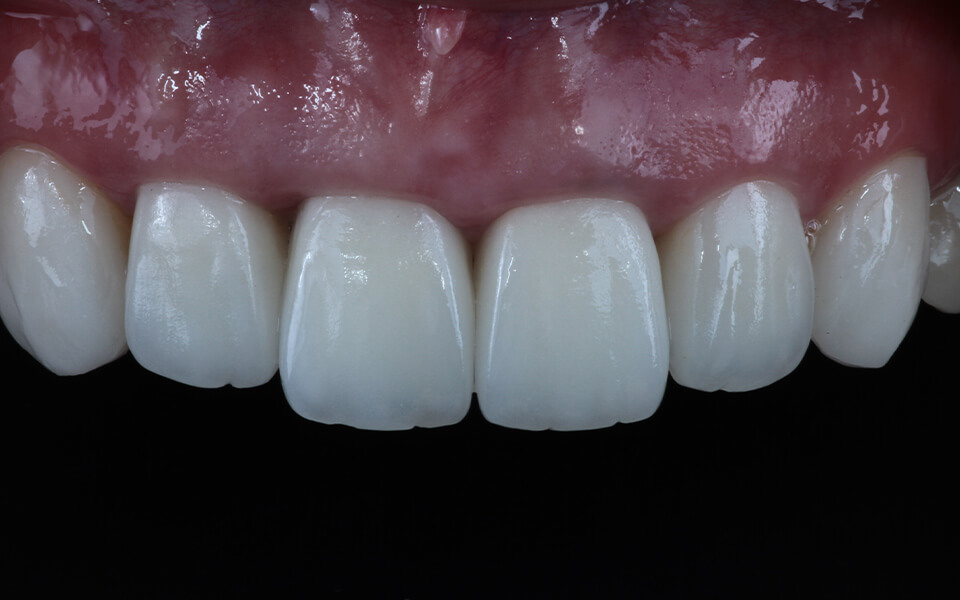

Case 01天然歯

ジルコニアレイアリング